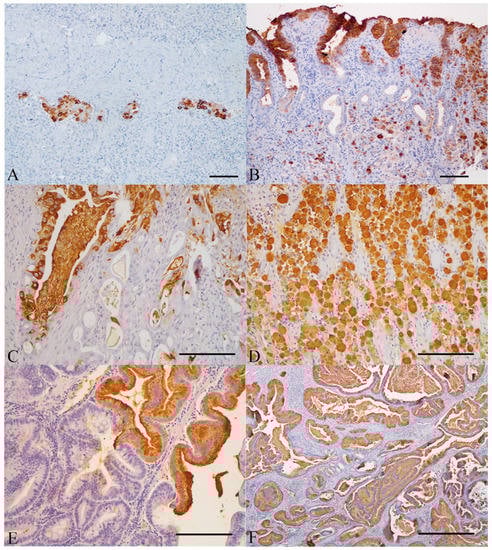

3.3.1. Normal Gastric Mucosa

3.3.2. Gastric Polyps

3.3.3. Non-neoplastic Gastric Mucosa Adjacent to Carcinomas

3.3.4. Gastric Carcinomas